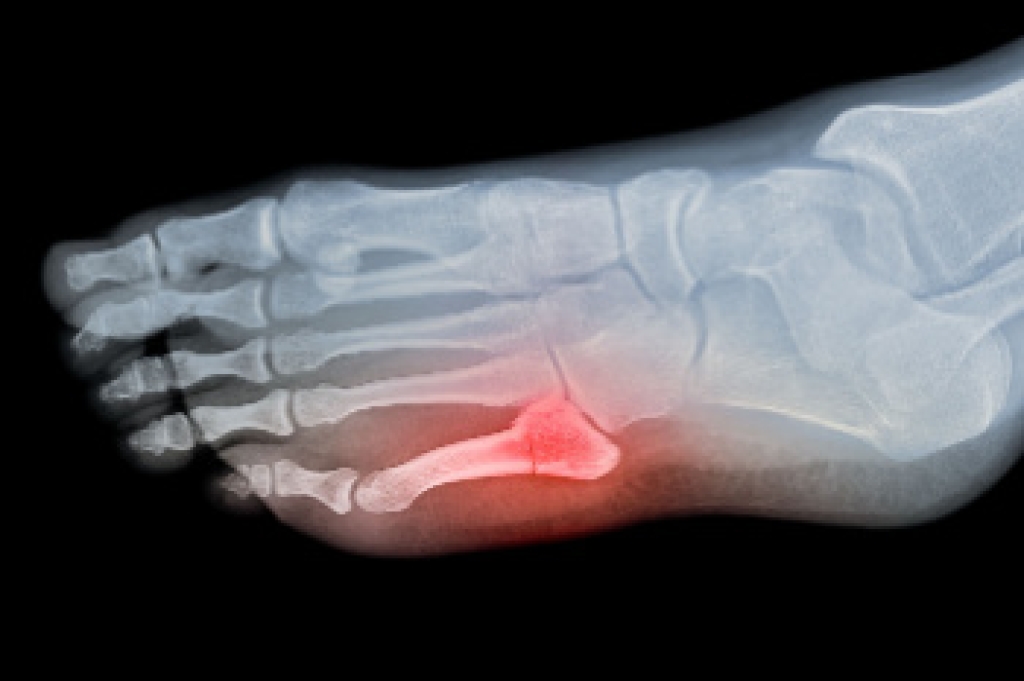

A toe fracture is a break in one of the small bones of the toe, often caused by trauma such as stubbing the toe, dropping something heavy on it, or sports injuries. Symptoms include pain, swelling, bruising, and difficulty walking. The affected toe may appear crooked or misaligned. Diagnosis typically involves a physical examination and imaging tests like X-rays to confirm the extent and location of the break. A podiatrist can assess the injury and recommend appropriate care, which may include splinting, protective footwear, or, in some cases, surgery. If you suspect a broken toe, it is suggested that you visit a podiatrist promptly to ensure proper healing and to avoid long-term complications.

Although most people try to avoid foot trauma such as banging, stubbing, or dropping heavy objects on their feet, the unfortunate fact is that it is a common occurrence. Given the fact that toes are positioned in front of the feet, they typically sustain the brunt of such trauma. When trauma occurs to a toe, the result can be a painful break (fracture).

Severe toe fractures may be treated with a splint, cast, and in some cases, minor surgery. Due to its position and the pressure it endures with daily activity, future complications can occur if the big toe is not properly treated.